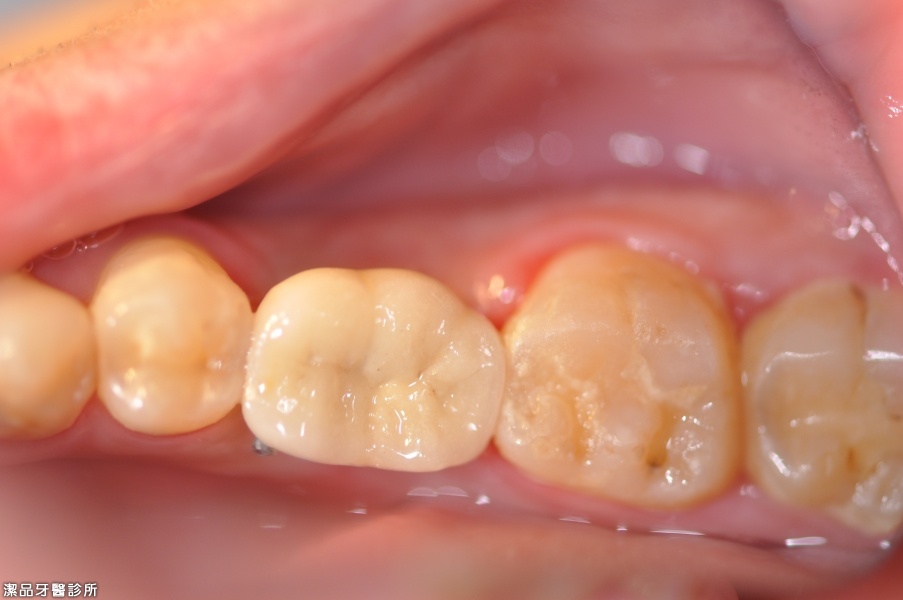

植牙後3個月完成治療

植牙周圍都是健康的骨頭